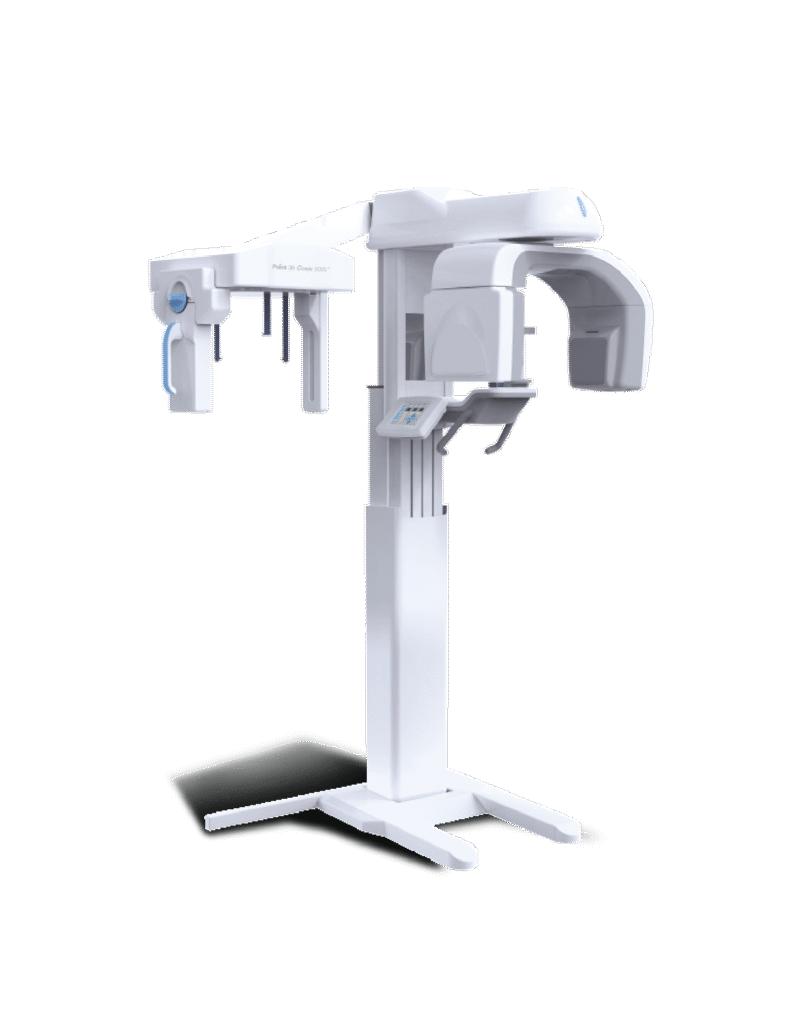

This provides a highly detailed, clear image of the teeth and jaw. It allows us to identify issues that may not be visible on a standard X-ray.